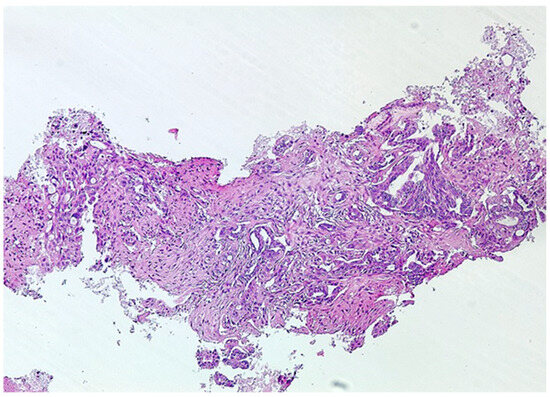

2.2. Cytohistological Evaluation